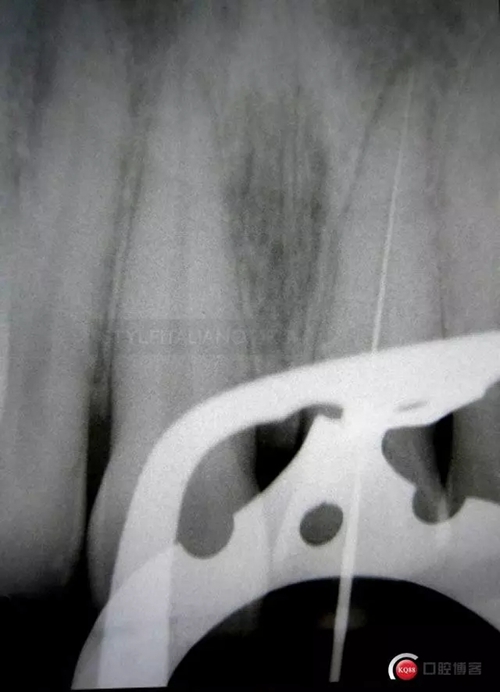

So, after the root canal treatment under the dam with correct pulp chamber opening, a cleaning of the cavity access and a root filling level control

617365.jpg